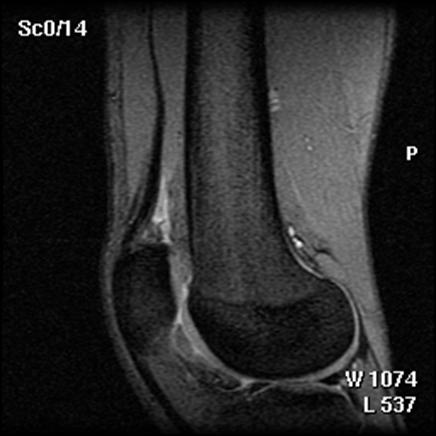

Fig.32. Imagine RMN pacient T.C. 19 ani

Fig.33. Imagine RMN T.C. 19 ani

Fig.34. A-scanare inaintea microfracturarii, B-scanare la patru luni dupaa microfracturare.

Evaluarea imaginilor RMN a fost realizata de catre radiologist cu experienta, care cunostea situatia pacientilor si operatia efectuata. Imaginile au fost astfel analizate incat sa se observe zonele cu cartilaj de reparare comparativ cu cel nativ. Repararea morfologica a fost descrisa ca depresiva, neteda, sau mareata comparativ cu cartilajul nativ inconjurator. Volumul de umplere al defectului cu cartilaj reparator a fost masurat folosind imagini sagitale si coronale si a fost gradat ca bun (intre 67% si 100%), moderat (34% la 66%), sau slab (0% la 33%) pe baza procentajului defectului umplut. Interfata cu suprafata cartilajului nativ adiacent a fost evaluata si gradata ca fiind mica ( gaura ≤ 2mm) sau mare (gaura ˃ 2mm). Edemul maduvei osului subcondral a fost gradat ca fiind usor (˂ 1 cm²), moderat (intre 1 si 3 cm²) sau sever (˃ 3 cm²), iar prezenta sau absenta cresterii osoase a fost atent inregistrata.